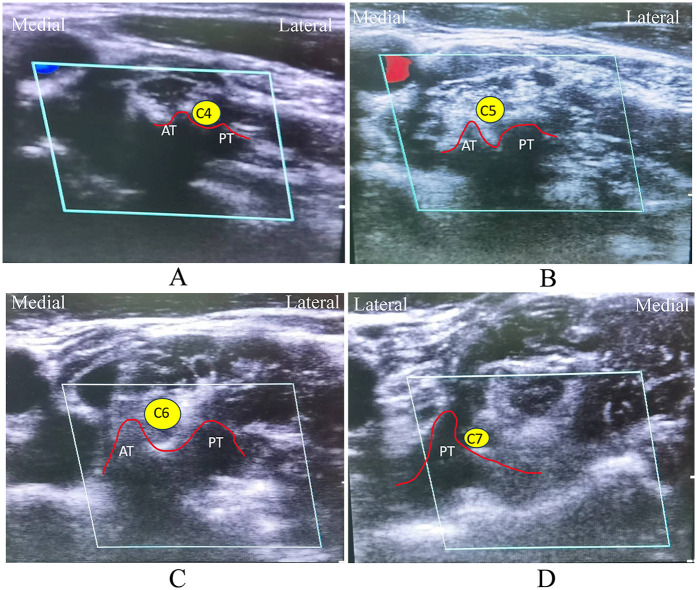

Background: The best treatment yielding clinical benefits was still equivocal and controversial for the treatment of cervical radicular pain (CRP). This study aimed to propose a novel combination strategy of percutaneous cervical nucleoplasty (PCN) and ultrasound-guided pulsed radiofrequency (PRF) of cervical nerve root for CRP, and to compare its therapeutic effects with PRF alone.

Methods: 120 CRP patients who satisfied the inclusion requirements between January 2016 and March 2019 were retrospectively analyzed and split into PCN + PRF and PRF groups. The propensity score matching (PSM) technique was used to correct the imbalanced confounding variables between the groups. Then, clinical outcomes including the visual analog scale (VAS) score, Neck Disability Index (NDI) score, clinical assessment scale for cervical spondylosis (CASCS), modified MacNab criteria, radiological parameters, and complications were evaluated.

Conclusion: We present and describe a novel strategy for the combined treatment of CRP in chronic cervical radicular pain using ultrasound-guided percutaneous disc radiofrequency ablation PCN and spinal nerve root pulse radiofrequency PRF, which is both effective and safe throughout the treatment process, reducing pain and improving function.